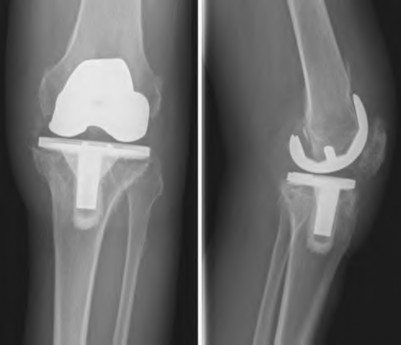

A 65-year-old woman with painful knee arthritis and the deformity seen in Figure A, is scheduled to undergo a total knee arthroplasty. All the following are risk factors for a post-operative peroneal palsy EXCEPT:

Figure A demonstrates and AP radiograph of the knee showing end-stage arthritis with severe lateral compartment narrowing.